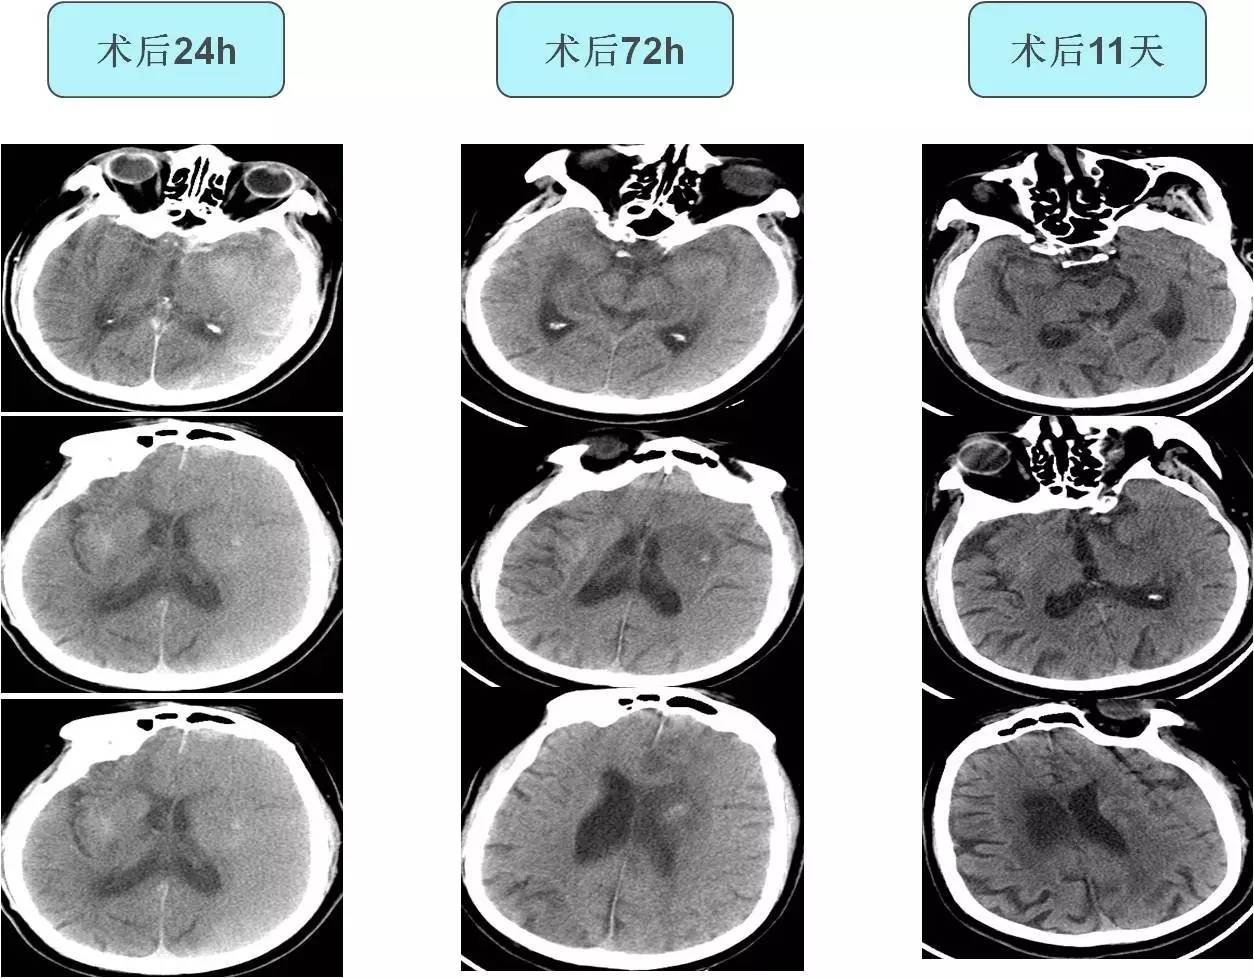

不同时间CT表现